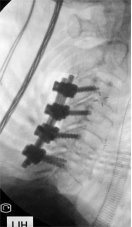

7. 复杂脊柱骨折内固定技术

随着区域内社会经济开发,复杂严重脊柱脊髓损伤病例增加,如何良好的手术治疗解除脊髓压迫、重建脊柱稳定性,使患者创伤最小、收益最大是促进患者康复至关重要的一环。好看视频下载

已熟练开展各类脊柱损伤修复重建技术,每年完成复杂脊柱骨折手术处于区域领先水平。